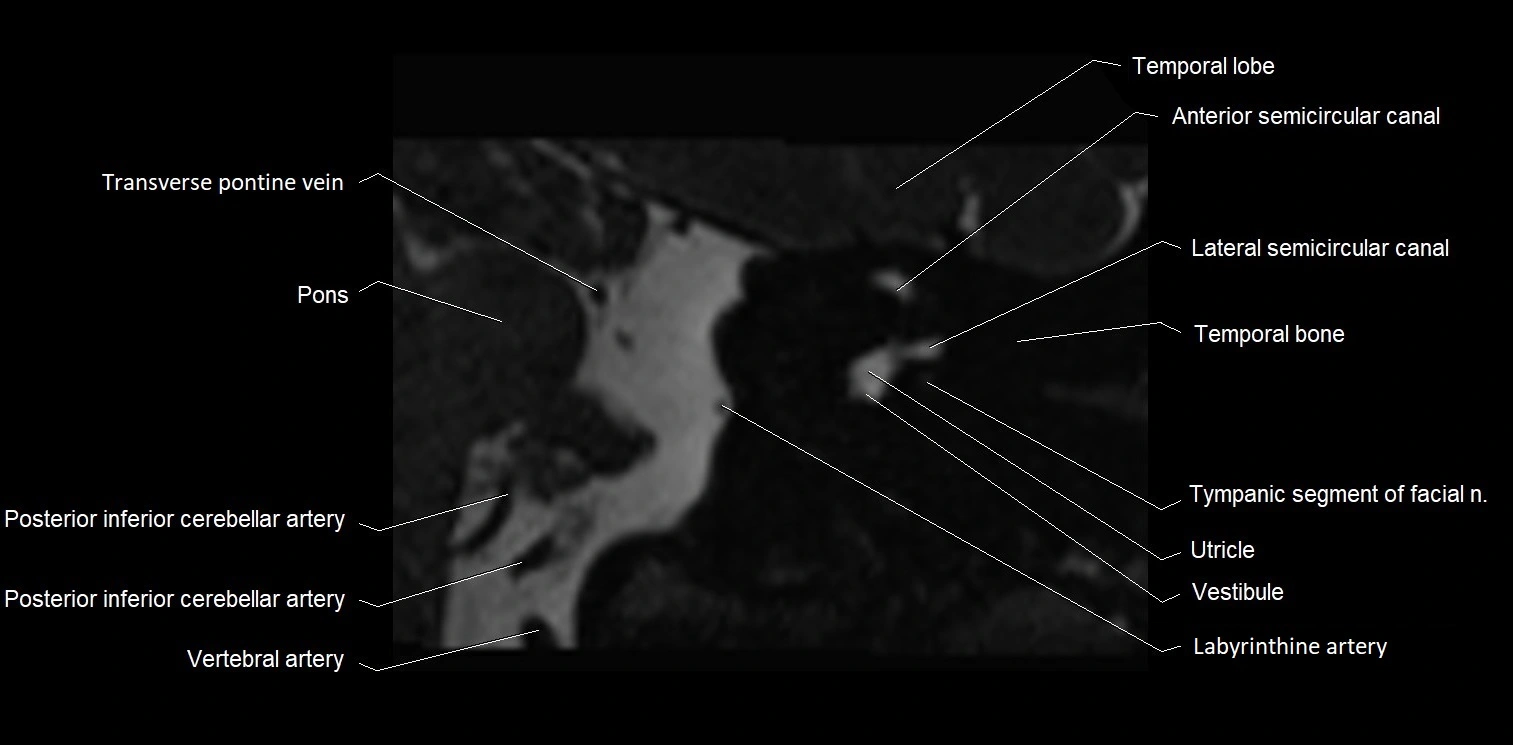

MRI images

image